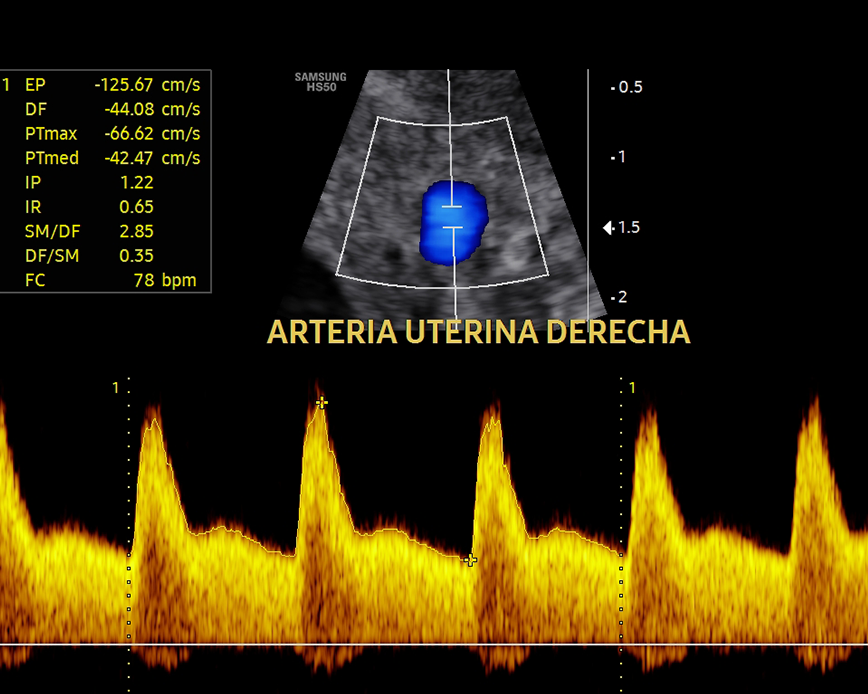

Esta ecografía sirve para evaluar la hemodinamia materno-fetal y detectar problemas de crecimiento como el RCIU (Restricción del Crecimiento Intrauterino) y el riesgo de preeclampsia (presión arterial alta durante el embarazo). Además, nos permite evaluar el cordón umbilical y detectar circulares de cordón simple, doble o triple.